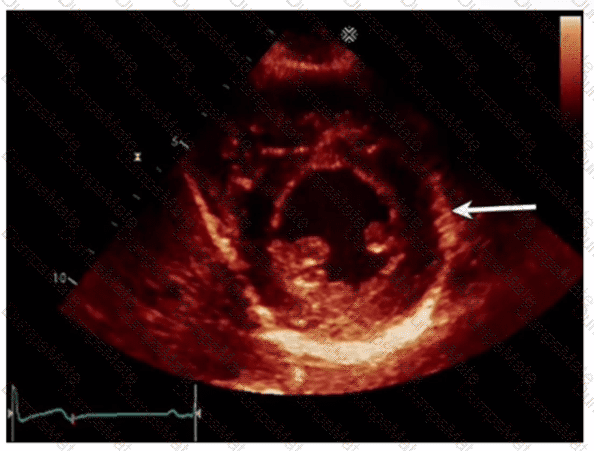

Which finding is shown in this image?

AE-Adult-Echocardiography Question 4

Options:

A.

Chiari network

B.

Left atrial thrombus

C.

Cor triatriatum

D.

Artifact